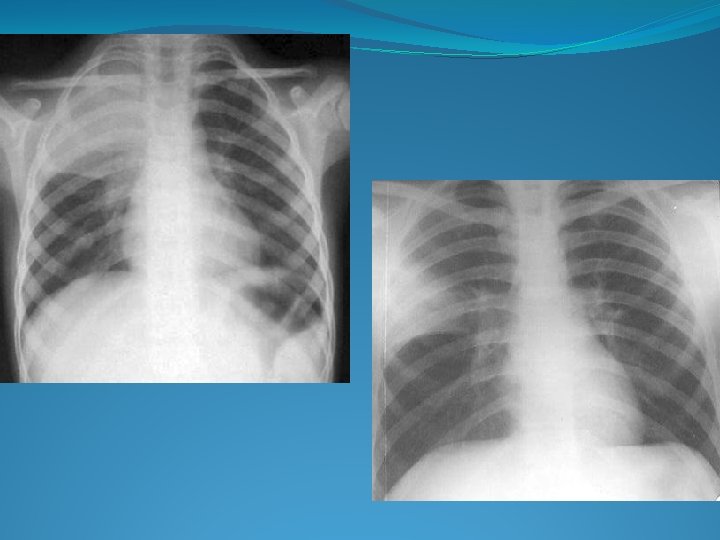

Bronhopneumonie Pneumonie lobară Reprezentarea schematică a bronhopneumoniei şi pneumoniei lobare

Radiologic: opacitati rotunde/ovalare, contur estompat, diseminate opacităţi multiple de intensitate medie, numeroase în câmpurile pulmonare medii şi bazale opacităţi difuze, mai frecvent in c. pulmonare superioare ca şi in regiunile parahilare

Bronhopneumonie lobulară confluentă